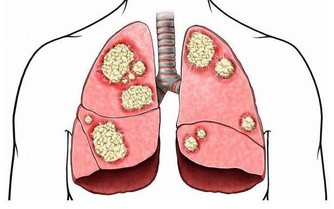

飯後一支煙,賽過活神仙?

吃飯犯10個錯,傷胃又致癌! 一天三頓這麼吃,身體可能越吃越差

飯後一支煙,傷肺又傷胃!

飯後,人體血液循環加快,血液對尼古丁吸收能力增強,人體處於興奮狀態,腦袋飄飄然,就如同“煙民”們描述“神仙”一樣的感覺。

但其實,飯後一支煙,比平常吸十支的毒害還大。因為身體在對食物消化吸收的同時,對香煙煙霧的吸收能力也增強,吸進的有害物質也增加。所以,飯後吸煙,禍害無邊。